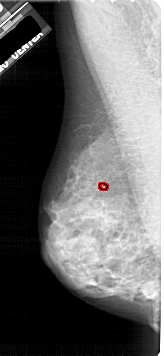

A_1914_1.RIGHT_MLO

RIGHT_MLO LINES 5491 PIXELS_PER_LINE 2431 BITS_PER_PIXEL 12 RESOLUTION 43.5 NON_OVERLAY

FILE: A_1914_1.LEFT_MLO.OVERLAY

TOTAL_ABNORMALITIES 1

ABNORMALITY 1

LESION_TYPE CALCIFICATION TYPE PLEOMORPHIC DISTRIBUTION CLUSTERED

ASSESSMENT 4

SUBTLETY 2

PATHOLOGY BENIGN

TOTAL_OUTLINES 1